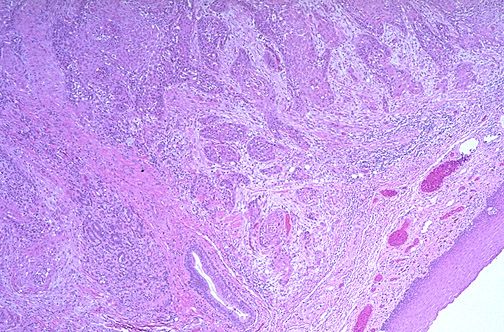

![]() | At low power, there is normal squamous mucosa at the lower right, but a squamous cell carcinoma is infiltrating the submucosa and muscularis of the tongue. Risk factors for oral cancers include: use of tobacco, alcoholism, prolonged irritation from ill-fitting dentures or irregular teeth, and chewing betel nut. |